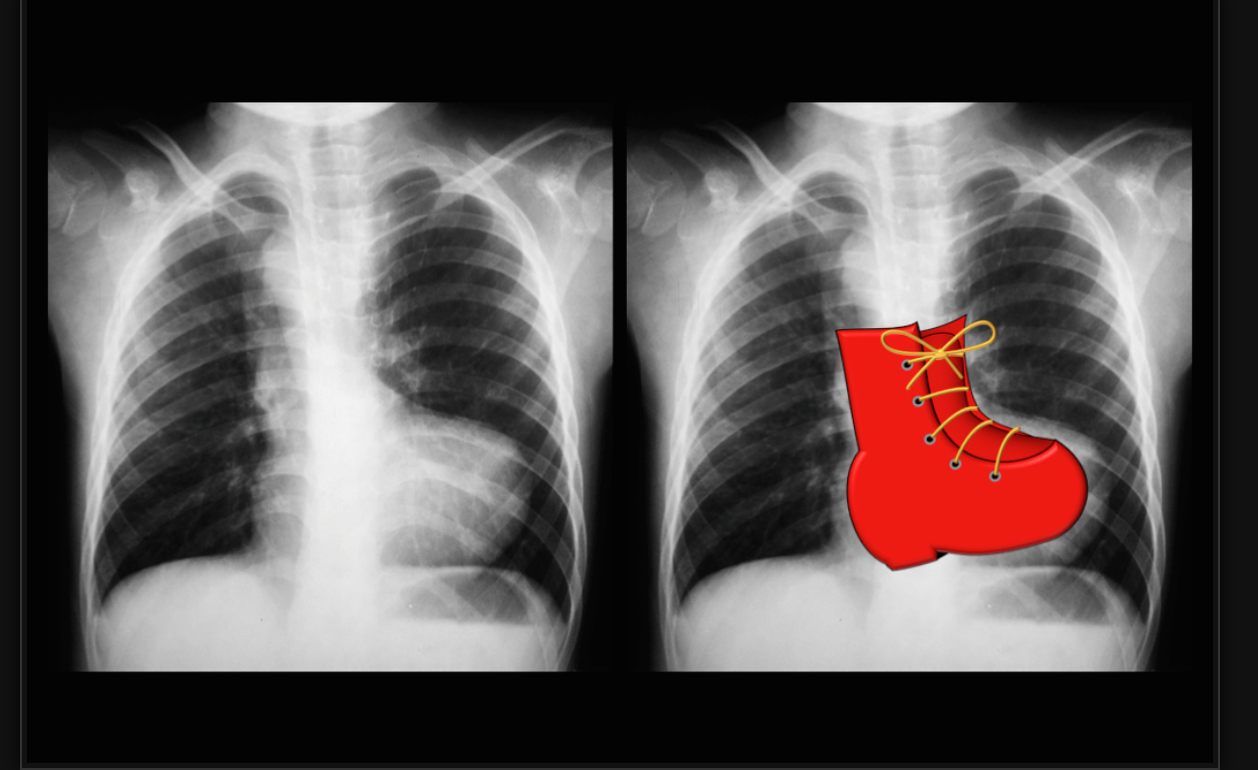

DDx of Boot shaped heart